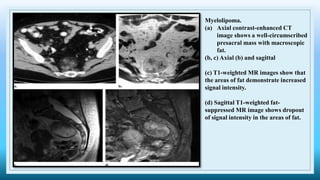

Myelolipoma.

(a) Axial contrast-enhanced CT

image shows a well-circumscribed

presacral mass with macroscopic

fat.

(b, c) Axial (b) and sagittal

(c) T1-weighted MR images show that

the areas of fat demonstrate increased

signal intensity.

(d) Sagittal T1-weighted fat-

suppressed MR image shows dropout

of signal intensity in the areas of fat.